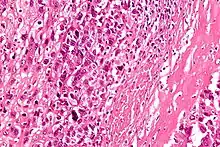

Microscopically: The characteristic feature of osteosarcoma is presence of osteoid (bone formation) within the tumor. Tumor cells are very pleomorphic (anaplastic), some are giant, numerous atypical mitoses. These cells produce osteoid describing irregular trabeculae (amorphous, eosinophilic/pink) with or without central calcification (hematoxylinophilic/blue, granular)—tumor bone. Tumor cells are included in the osteoid matrix. Depending on the features of the tumor cells present (whether they resemble bone cells, cartilage cells, or fibroblast cells), the tumor can be subclassified. Osteosarcomas may exhibit multinucleated osteoclast-like giant cells.[21]